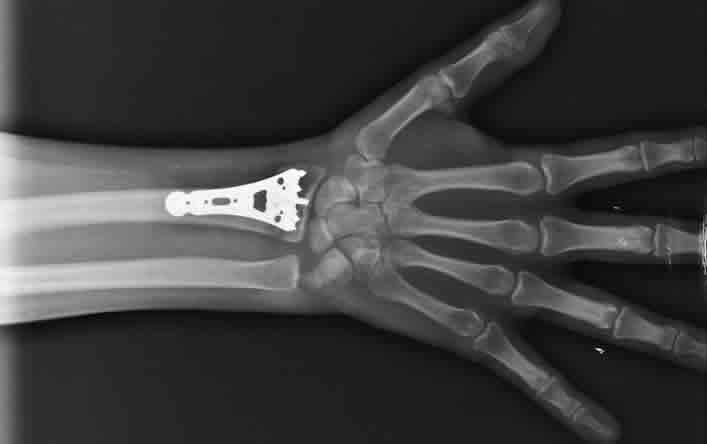

Fracturas de huesos y columna

Atención especializada en el manejo de fracturas y luxaciones (dislocación) en extremidades o columna vertebral secundarias a golpes, caídas, accidentes automovilísticos o actividades deportivas.

Manejo de fracturas simples mediante tratamientos conservadores con manipulación e inmovilización de la región afectada.

En caso de fracturas complejas o expuestas se ofrece la realización de cirugías.

Tratamiento inicial y seguimiento de pacientes con disminución o fragilidad ósea mediante el uso de medicamentos para aumentar la densidad y fortalecer los huesos, con el objetivo de prevenir las fracturas por caídas o golpes en muñeca, cadera y columna.